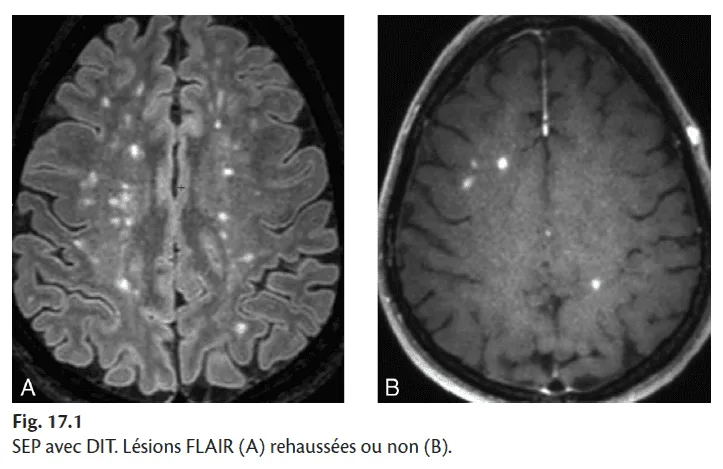

dissémination temporelle (DIT) définie par au moins deux épisodes cliniques séparés d'au moins un mois, ou des bandes oligoclonales dans le LCR, ou l'association en IRM de lésions anciennes et de lésions récentes (rehaussées par le gadolinium), ou l'apparition d'une ou plusieurs nouvelles lésions sur une IRM de contrôle (fig. 17.1) ;

Fig. 17.1

Il décrit les différentes lésions en FLAIR et en T1 injecté et leur topographie, en apprécie le nombre ce qui définit la charge lésionnelle, et analyse l'évolutivité de la maladie (logiciel de comparaison) en précisant l'apparition de nouvelles lésions (augmentation de la charge lésionnelle), lésions prenant le contraste ± en hypersignal diffusion (signe d'activité IRM de la maladie), apparition d'une atrophie cérébrale (voir fig. 1.13). À noter que dans le cadre d'un suivi régulier, on peut s'affranchir de l'injection de gadolinium si la charge lésionnelle est stable ainsi que la symptomatologie clinique.